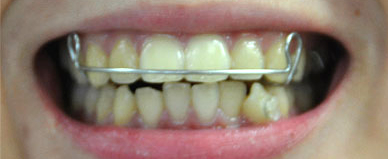

吉本歯科医院で矯正治療、いわゆる歯並びを治す治療、小さいお子さんが歯がガタガタで噛めないとか、そういう場合には将来、矯正装置をはずす前に「親知らずを抜く」ということが条件です。

「親知らず」を抜かない、ということであれば、矯正治療をスタートすることはできません、と、そこまで申し上げています。